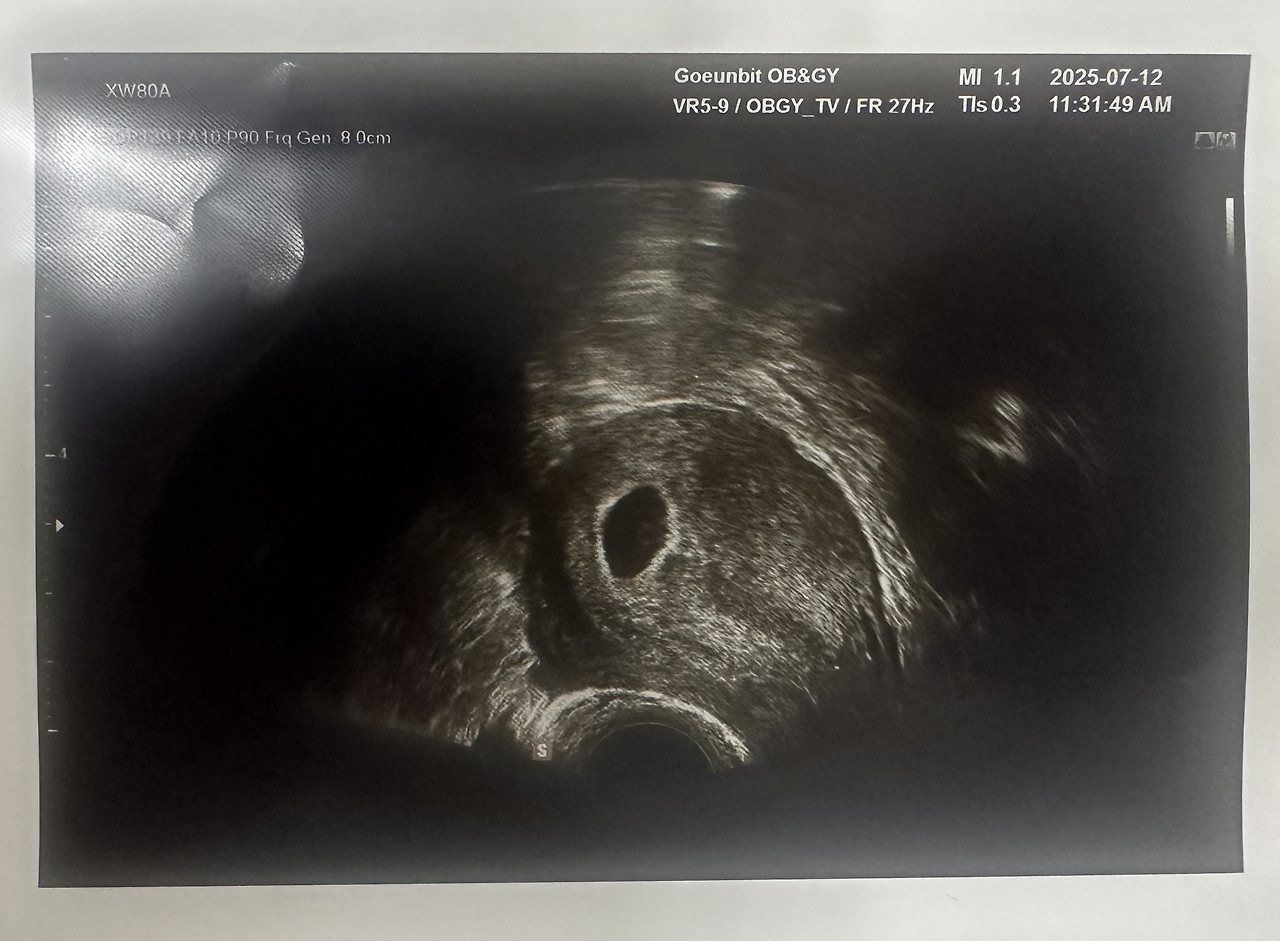

초음파 화면에는 작은 점 하나.

그게 아기집이라고 했다.

아직 심장은 뛰지 않았다.

7주2일 (1).jpg 7주 2일 차

7주2일 (5).jpg 7주 2일 차